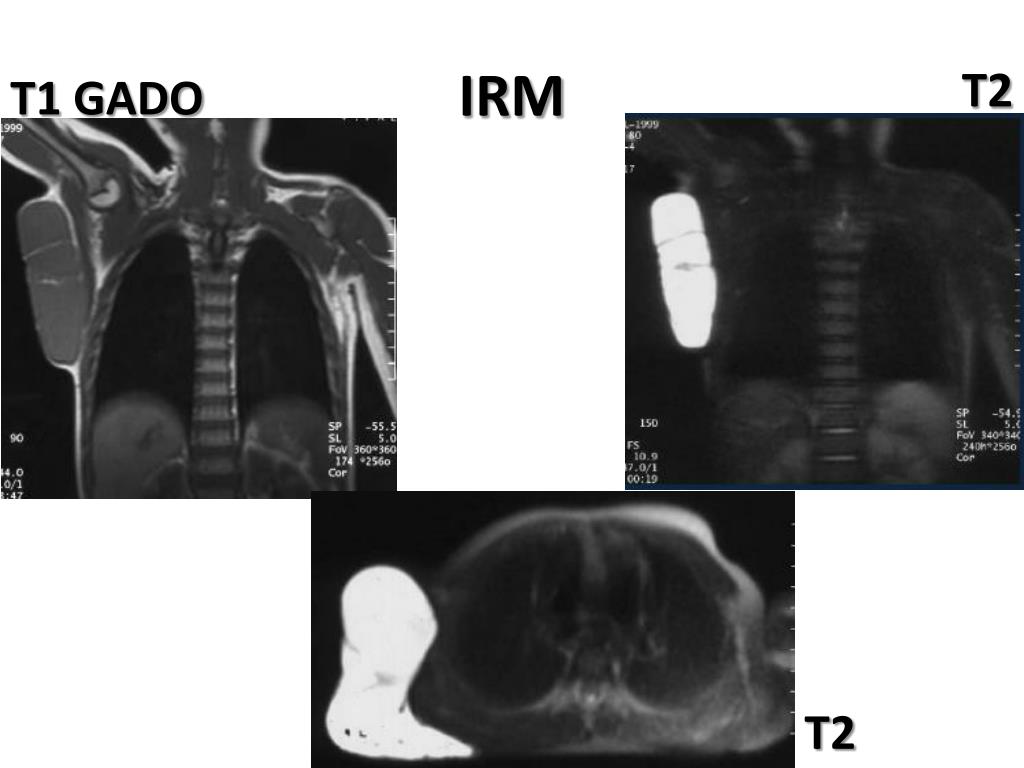

18. IRM • Bilan pré-op (caractère infiltrant des MV? / rapports avec organes de voisinage). • HypoT1- hyperT2 • Rehaussement lent et progressif des lumières vasculaires (séquences tardives+++). • Structures hypoT1-T2 (phlébolithes, septa fibreux ) • Prolifération graisseuse et atrophie musculaire en cas de MV intramusculaires (discuter angiosarcome, liposarcome) mais pas de vaisseaux nourrissiers.

19. IRM T2 T1

20. IRM T1 GAD T2 T1